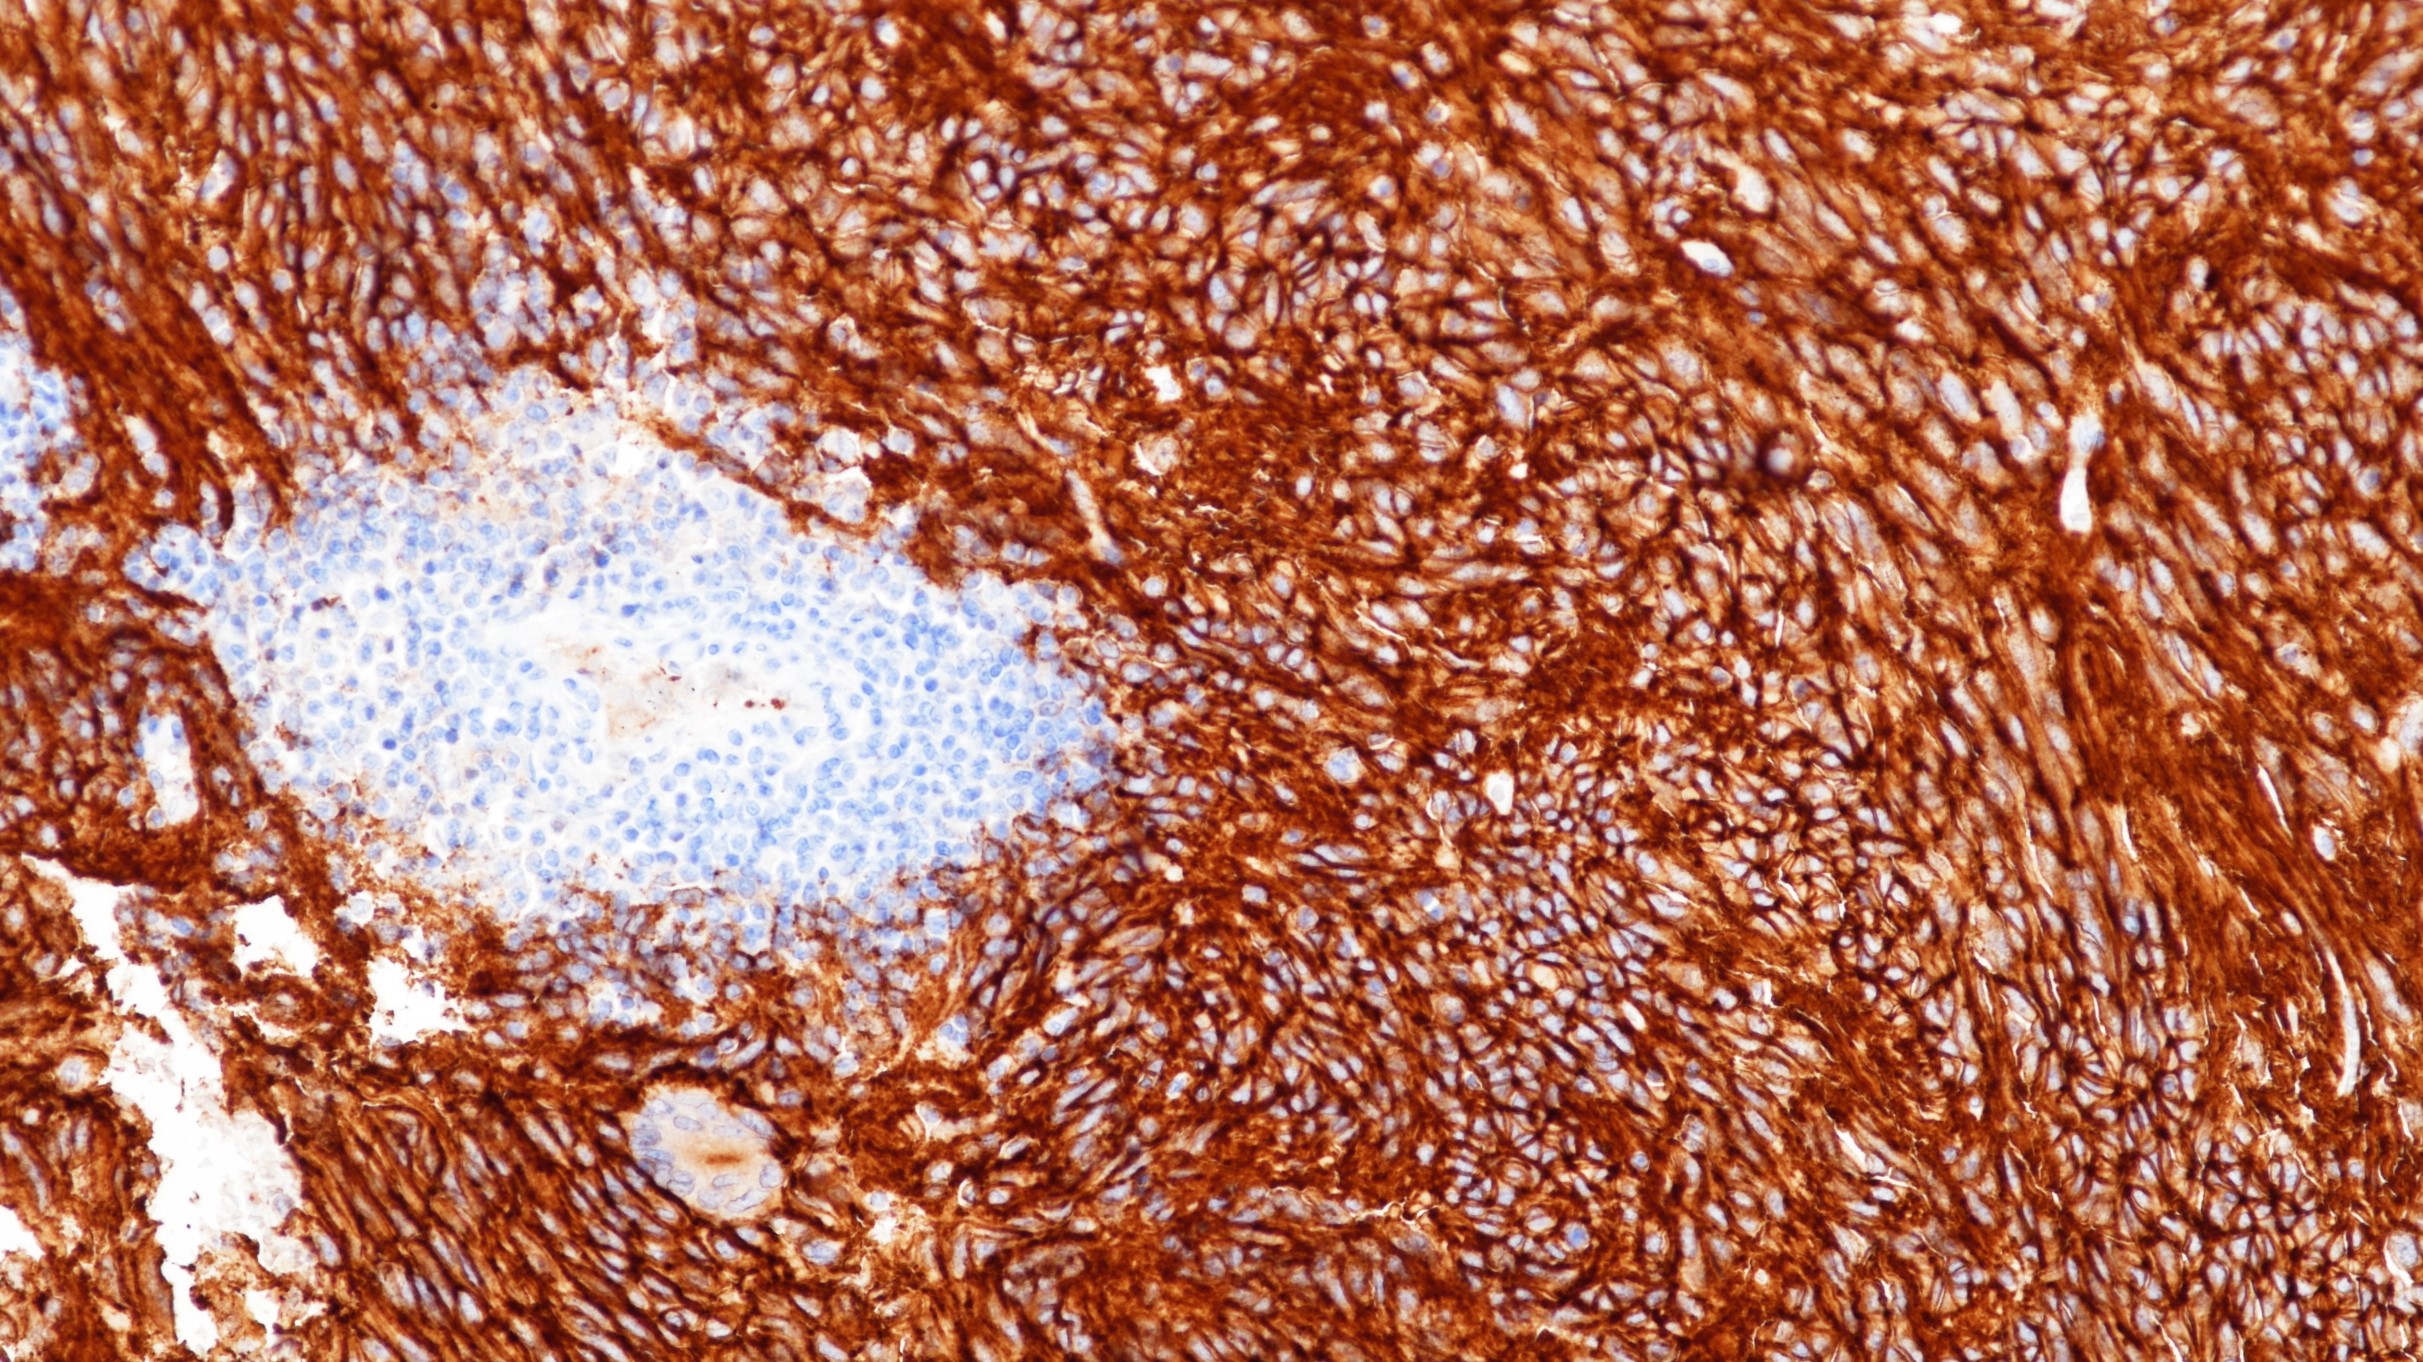

2. Rizzo F M , Palmirotta R , Marzullo A , et al. Parallelism of DOG1 expression with recurrence risk in gastrointestinal stromal tumors bearing KIT or PDGFRA mutations[J]. Bmc Cancer, 2016, 16(1):87.

3.中华医学会.《临床技术操作规范·病理学分册》.人民军医出版社,2004.